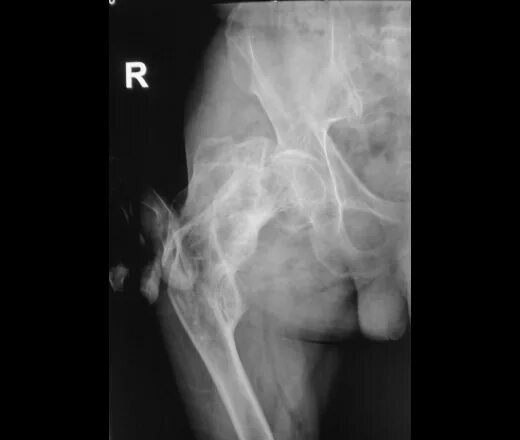

Рентген тазобедренный в двух проекциях